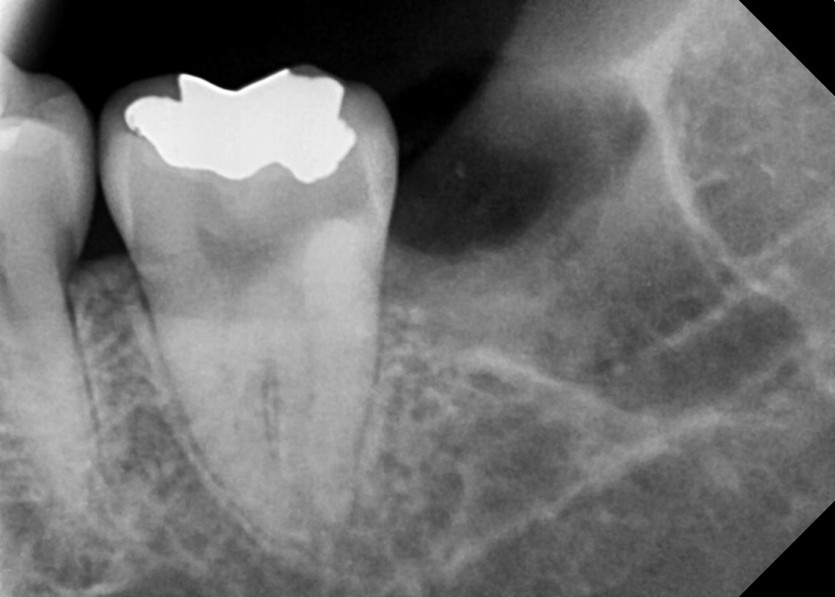

#38 사랑니 발치

구강 외과 전문의가 당일 발치했습니다.